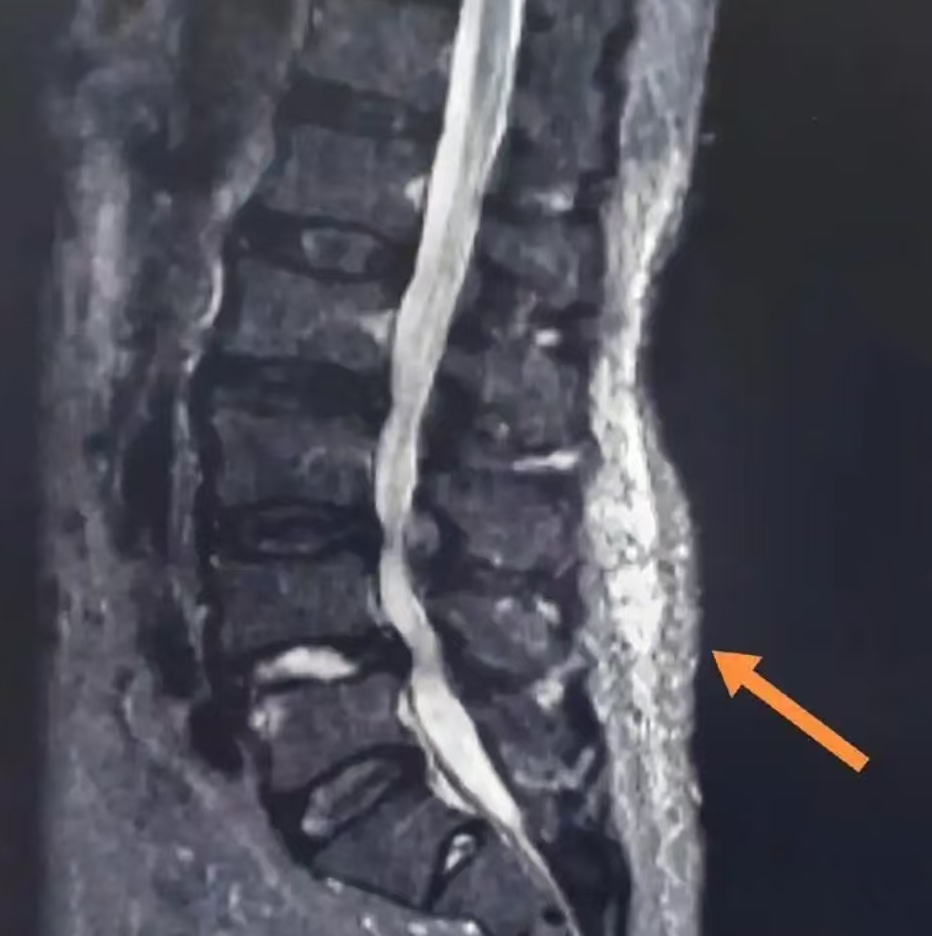

那这个病咋确诊?是不是全靠医生摸?

主要是通过医生仔细触诊,找到具体的压痛点,通常可以发现伴有相应的动作受限。

但是现在可先进多啦!还可以通过高频超声、MRI弹性成像这些“高科技雷达”,能把藏在里面的病灶照得一清二楚,误诊漏诊?勿可能的事!